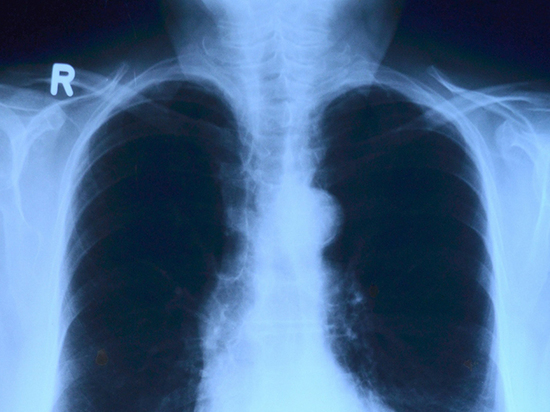

«Все симптомы дыхательной недостаточности и бронхо-легочной патологии: одышка, кашель, температура, мокрота», — заявил Пурясев в комментарии для радиостанция «Говорит Москва».

Ранее от коронавируса скончался ведущий программы «Русское лото» Михаил Борисов. Мужчина жаловался на затруднённое дыхание, но от госпитализации отказался. Позднее ведущего все же отвезли в больницу, где подключили к аппарату ИВЛ. Оказалось, что у него было поражено 75% легких. К сожалению, врачи оказались бессильны.